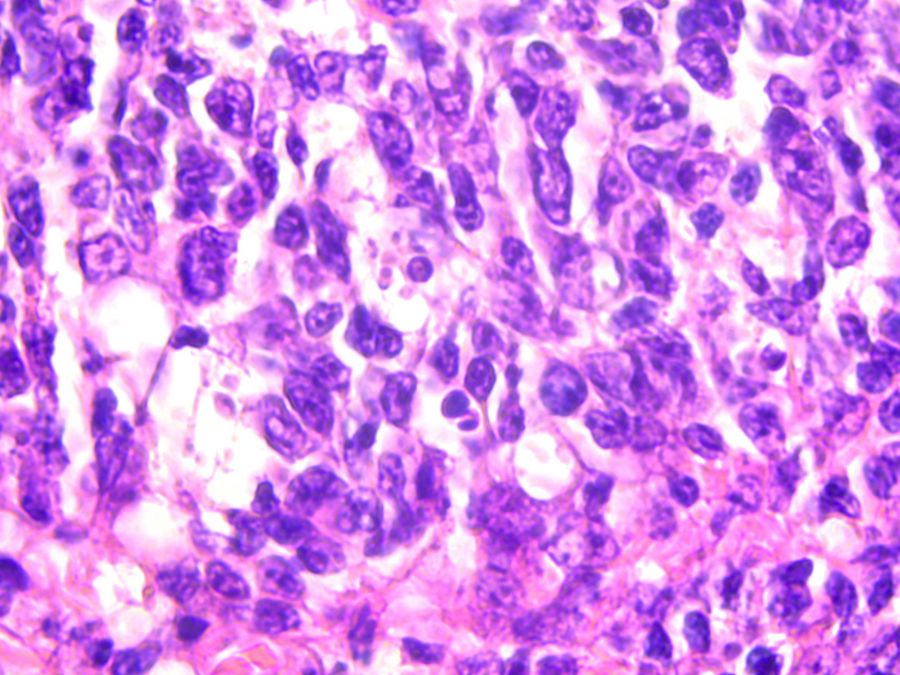

Precision in Histopathology

For the histopathologist, the microscope is the essential tool for tissue visualization, helping with identification of cellular and tissue-level changes that are the very signature of disease.

Microscopy in Cytopathology: Integral to Early Detection

In cytopathology, the microscope represents the primary gateway to understanding cellular changes, enabling cytopathologists to precisely visualize and interpret individual cells, clusters, and their intricate arrangements. This direct, high-resolution cellular analysis is fundamental for the early detection, accurate diagnosis, and effective management of a broad spectrum of diseases, often with minimal patient invasiveness.